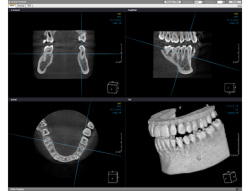

当院では、3D撮影ができる歯科用CTを導入しています。

従来のレントゲンは2次元の平面図でしたが、歯科用CTでは、3次元で細部まで鮮明に映し出すことができるので、より正確な診断が可能となりました。

3次元画像解析システムで治療シミュレーションを行います。

歯科用CTにより3次元で撮影した画像を、PC上で画像解析し、歯の神経や骨の状態を細部まで分析します。